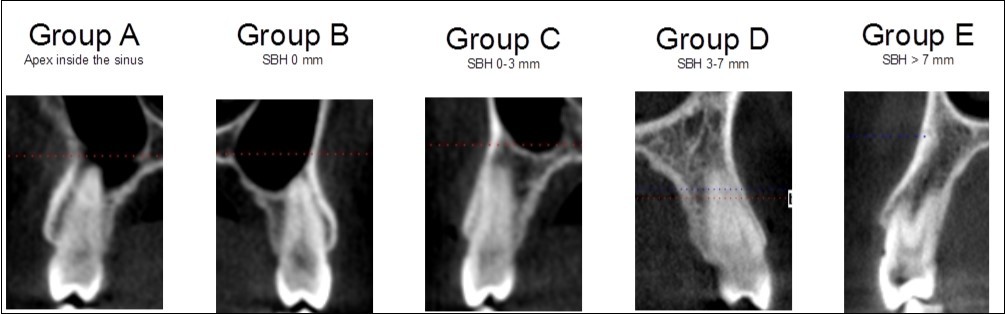

Findings for the premolars were classified into five groups, as follows:

1. The root apex was located inside the sinus (Group A)

2. The distance of the root apex from the sinus floor was 0 mm with the root apex, but not penetrating in the sinus (Group B)

3. The distance was 1 to 3 mm (Group C)

4. The distance was 3 to 7 mm (Group D)

5. The distance was more than 7 mm (Group E)

Figure 1 presents examples of each of the five categories.

Figure 1.Classification in five different categories for premolars